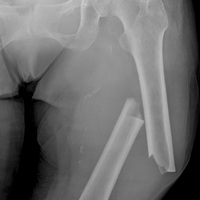

Участниками данной работы стали 2064 пациента, перенесших хирургические вмешательства, направленные на уменьшение массы тела. Их состояние сравнивали с уровнем здоровья 5027 пациентов с ожирением, которым не выполняли подобные операции. В целом, ученые отметили, что бариатрические операции приводили к повышению риска переломов костей на 21%. Наибольший риск был у тех пациентов, которые проходили мальабсорбтивные процедуры, препятствовавшие физиологическому усвоению пищи, например шунтирование желудка. У таких участников в течение 12 лет после проведенной операции риск переломов был на 47% выше, чем у пациентов с ожирением, не получавших оперативное лечение. Выясняя, что же именно определяет повышенный риск переломов — мальабсорбтивный тип операций или уменьшение количества потребляемой пищи, ученые определили, что при вмешательствах рестриктивного типа, ограничивающих объем пищи, риск снижения плотности костной ткани значительно ниже, чем при нарушающих всасывание и усвоение.

Комментируя данную работу, доктор Эндрю Даффи (Andrew Duffy), директор Американского центра бариатрической и метаболической хирургии, отметил, что было бы интересно узнать, какие витаминно-минеральные препараты принимали пациенты до и после проведения хирургических вмешательств. Он подчеркнул, что у участников исследования отмечали переломы длинных трубчатых костей, а не позвонков, что более характерно для остеопороза. Возможно, переломы конечностей связаны с большей физической активностью пациентов после операций. Тогда как снижение плотности костной ткани у значительно похудевших пациентов является абсолютно естественным явлением. Худея, человек неизбежно теряет некоторое количество мышечной и костной ткани. Эта потеря не является патологической и не способна в значительной мере повышать риск переломов костей. Несмотря на это, ученый считает обоснованным назначение витаминно-минеральных комплексов пациентам, перенесшим операции, направленные на уменьшение массы тела.